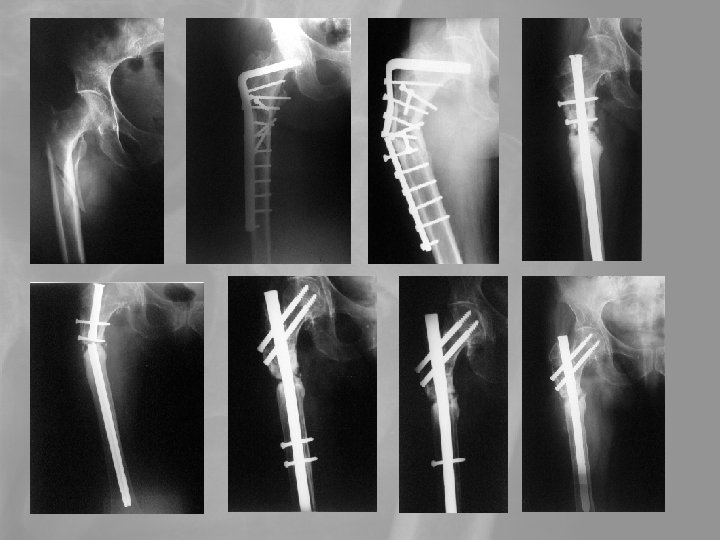

5. Medence, csípótáji törések A csípőtáji törések a leggyakrabban előforduló időskori törések. A tokon belüli törés szövődménye a fejelhalás, ami az esetek 25 -35 %-ában bekövetkezik. A tokon kívüli törések gyógyhajlama jó. A leggyakoribb szövődmény a thromboembolia, mely a az első postoperatív évben 20 -25%-os halálozással jár.

5. Medence, csípótáji törések. Az időskori sérülések halálos szövődményei több mint 50%-ban ebből a csoportból kerülnek ki. > peremtörés, szemérem- és az ülőcsont szártörései, Konzervatív kezelés < transacetabularis törések Operatív/konzervatív kezelés

Delayed revision 73 y female. Failed primary stabilisation, Delayed septic complication Pyarthros coxae, septic diaphyseal nonunion. Exarticulation?

Delayed revision Op. sec. Girdlestone+open plate-osy. Secondary wound granulation